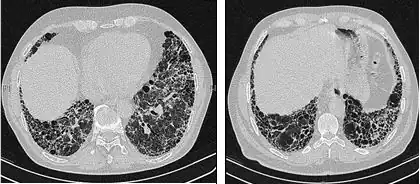

Die radiologische Untersuchung mittels HRCT ist ein grundlegendes Element der IPF-Diagnose. Ein HRCT wird mit einem konventionellen Computertomographen ohne Injektion eines Kontrastmittels durchgeführt. Die Schnittbilder zur Auswertung sind sehr dünn (1–2 mm).

Ein typisches Thorax-HRCT bei IPF weist fibrotische Veränderungen beider Lungenflügel auf, vor allem im Bereich der Basis und der Peripherie. Gemäß der gemeinsamen ATS/ERS/JRS/ALAT-Richtlinien von 2011 ist das HRCT ein maßgeblicher Bestandteil im diagnostischen Prozess der IPF, da es eine UIP bei Vorliegen folgender Merkmale identifizieren kann:[1]

- Retikuläre Verschattungen, die oft mit Traktionsbronchiektasie einhergehen

- Honigwabenmuster, gekennzeichnet durch Ansammlungen zystischer Lufträume, die meistens einen vergleichbaren Durchmesser haben (3–10 mm), gelegentlich aber auch größer sind. Sie liegen für gewöhnlich subpleural und sind durch klar abgegrenzte Wände und das Auftreten in mindestens zwei Reihen gekennzeichnet. Eine Reihe von Zysten reicht nicht aus, um als Honigwabenmuster bezeichnet zu werden.

- Milchglasverschattungen sind häufig, doch weniger ausgedehnt als die Netzstruktur.

- Die Verteilung ist typischerweise basal und peripher, jedoch häufig auch fleckförmig.